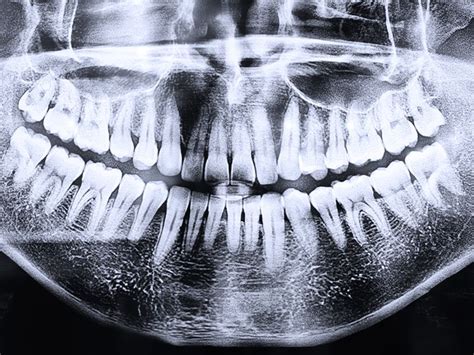

La resonancia magnética (RM) utiliza un campo magnético potente para generar imágenes detalladas de los tejidos del cuerpo. Esto hace que muchos pacientes teman que los implantes dentales puedan moverse o calentarse. La radiología es una especialidad médica que se encarga de tomar imágenes del interior del cuerpo mediante diferentes agentes físicos como son los rayos x o los campos magnéticos.

A diferencia de las radiografías, las resonancias magnéticas se realizan con ondas de radio y campos magnéticos, con el fin de conseguir imágenes anatómicas de una parte del cuerpo. En el caso de las resonancias magnéticas, en las que no se utilizan radiaciones ionizantes como en las tomografías computarizadas o en las radiografías convencionales, sino que se usan ondas de radio y campos magnéticos para generar imágenes anatómicas de una parte del cuerpo, el paciente debe estar libre de objetos metálicos extraíbles como monedas y llaves, ya que los objetos metálicos pueden causar riesgos para su seguridad.

El tipo de metal utilizado en odontología ha cambiado con el tiempo. Los implantes dentales son estructuras que se colocan en el hueso maxilar o mandibular para reemplazar dientes perdidos. Están hechos, generalmente, de titanio, un material reconocido por su durabilidad y compatibilidad con el cuerpo humano. Generalmente, se utiliza el titanio debido a su biocompatibilidad y resistencia. El titanio es no ferromagnético, lo que significa que no se ve afectado por los campos magnéticos de la RM.